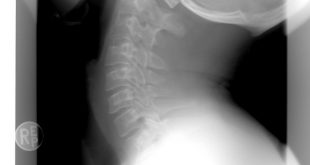

Devamı...BOYUN FITIĞI BELİRTİLERİ VE TEDAVİ YÖNTEMLERİ

Omurga omur (vertebra) adı verilen 33-34 kemikten oluşur. Kafatasının hemen arkasından başlayıp kuyruk sokumuna kadar uzanır.